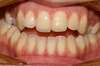

Intra Orale Droite

Intra Orale Face

Intra Orale Gauche